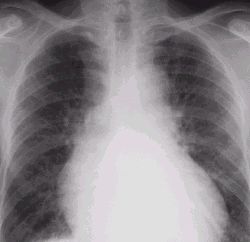

pulmonary congestion.jpg